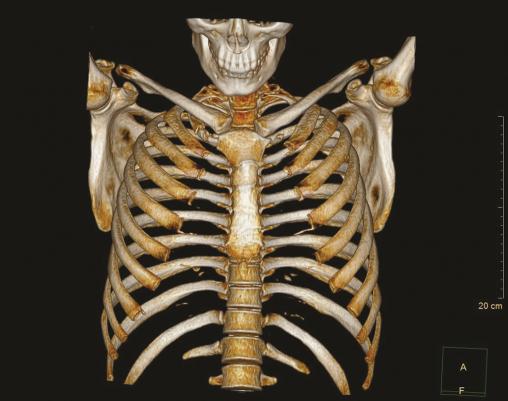

Ce jeune engagé de 21 ans consultait pour une douleur persistante du membre supérieur gauche avec hypotonie, hypoesthésie et paresthésie pour tous mouvements bras levé gauche et lors du port d’un sac à dos. L’examen clinique au repos était sans particularité. Le test d’Allen (position « haut les mains », menton levé, rotation controlatérale de la tête, inspiration profonde) et le test de Roos (position « haut les mains », mouvements lents de fermeture et ouverture de la main) étaient positifs dès 40 secondes avec reproduction de symptômes. Les tests musculaires étaient normaux. L’imagerie (radiographie cervicale [fig. 1], arthrotomodensitométrie [fig. 2], angio-imagerie par résonance magnétique [IRM] et électromyogramme [EMG]) montrait des côtes cervicales surnuméraires. Le bilan neurovasculaire était normal. Une simple éviction des situations à risque avec rééducation a résolu la doléance.

Une côte cervicale surnuméraire est présente chez 0,5 % de la population ; 10 % des patients sont symptomatiques et 9 % justifient une décompression chirurgicale.1 Lié à la compression du plexus brachial, le tableau clinique prend la forme d’un syndrome du conflit thoracique très variable (douleur, paresthésie, faiblesse du membre) lors de l’élévation prolongée du bras. Les tests cliniques sont peu spécifiques et sensibles et justifient de les associer (Adson, Allen, Roos). L’imagerie réalisée comprend radiographie cervicale, IRM et EMG notamment. Une kinésithérapie (protocole de Peet), des injections de corticoïdes, voire une chirurgie de décompression (scalénectomie, exérèse costale) peuvent être nécessaires.2